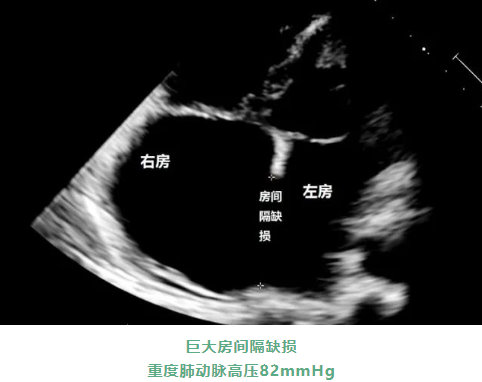

59岁的彭姨,长期以来一直都有呼吸困难和乏力等症状,近日因病情严重,到梅州市人民医院心脏血管外科就诊。经检查和询问病情,才知道彭姨患有先天性心脏病巨大房间隔缺损,后因病情拖延,心脏又出现二尖瓣关闭不全、三尖瓣关闭不全以及心房颤动等问题。

而且因患者的房间隔缺损非常明显,导致严重的肺动脉高压,即“艾森曼格综合征”,由于肺动脉压力高于体循环压力,心脏血流分流方向发生改变,该疾病是先天性心血管畸形的一种晚期状态。以往该病被看作是无法手术的“心脏绝症”、“生命杀手”,患者将面临心力衰竭、脑梗的风险。